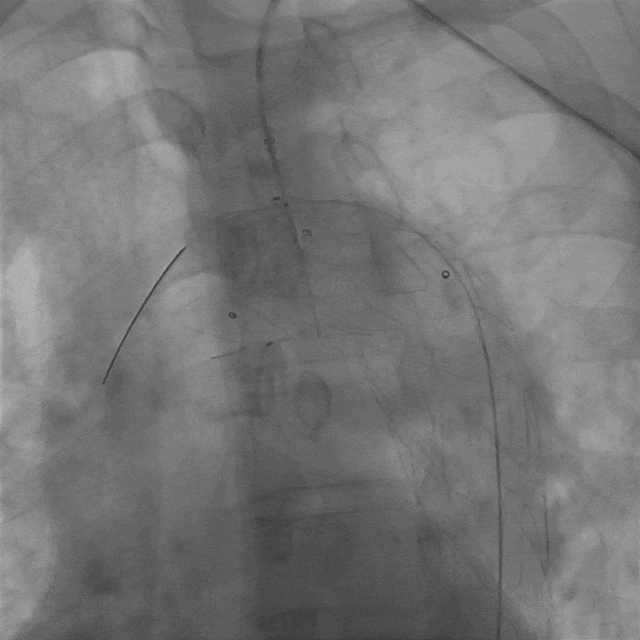

02. 交换0.035"Lunderquist超硬导丝至升主动脉,于左侧颈总动脉开口远端精确定位并释放华脉泰科PTBS3430180覆膜支架。造影提示主动脉溃疡隔绝完全,无内漏。

泥鳅导丝怎么用曲乐丰教授团队:0.018"和0.035"普通泥鳅导丝行胸主动脉弓上分支原位开窗的病例分享_https://www.jmylbn.com_新闻资讯_第9张

植入华脉泰科覆膜支架

泥鳅导丝怎么用曲乐丰教授团队:0.018"和0.035"普通泥鳅导丝行胸主动脉弓上分支原位开窗的病例分享_https://www.jmylbn.com_新闻资讯_第10张

释放华脉泰科支架前三节,再次造影确认位置